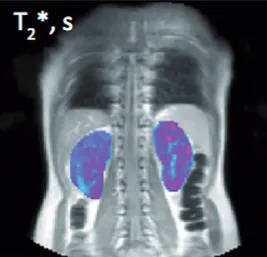

Bioxydyn is also experienced in using MRI biomarkers of inflammation and fibrosis in kidney disease. Examples include measurements of perfusion derived from arterial spin labelling (ASL), relaxation time measurements (T1, T2, T2*), volume measurements, diffusion MRI (ADC, FA). We are also experts in methods to measure hypoxic status (BOLD, oxygen-enhanced MRI) and pH (CEST).

The image shows maps of T2* in the kidneys of an individual with lupus nephritis. From Skeoch et al 2017.